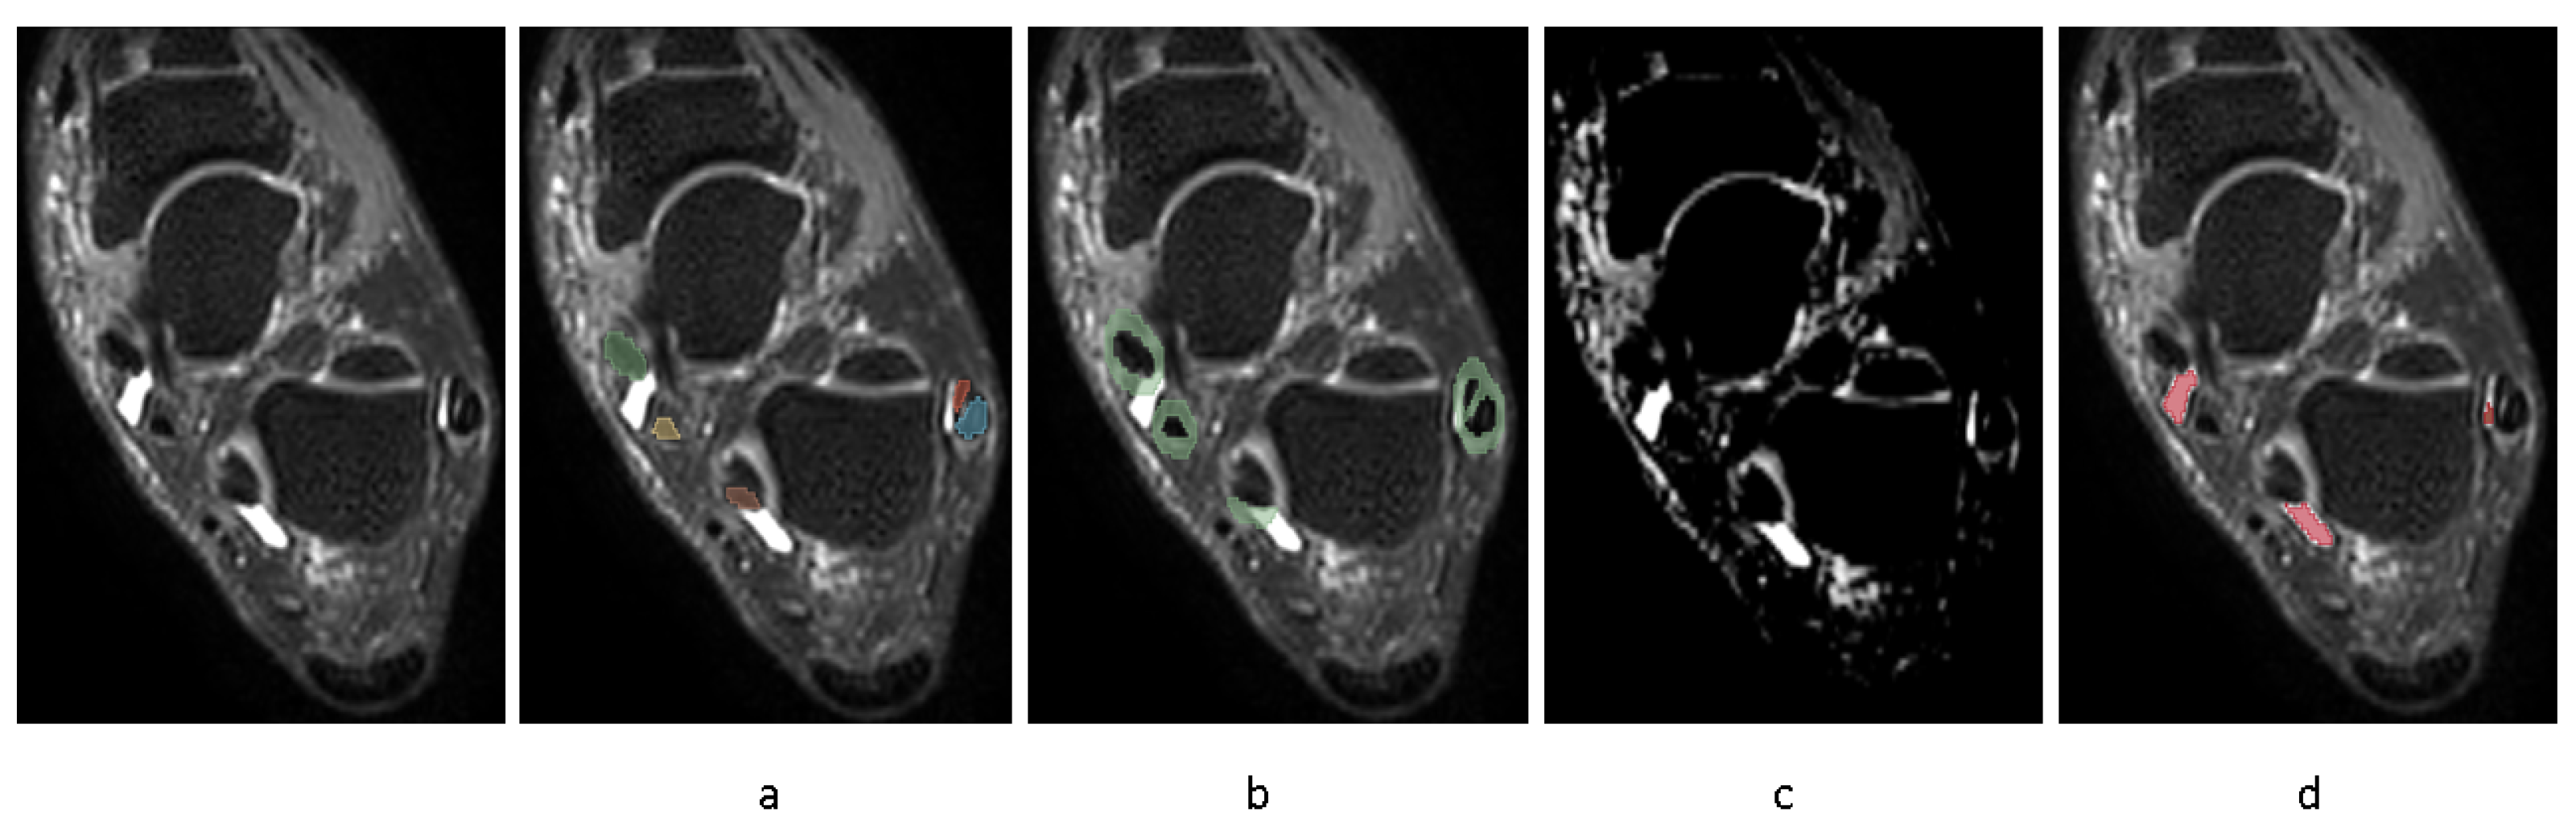

A representative segmentation of four tendon regions is demonstrated in Figure 3.

Evaluating the model’s performance with the Dice coefficient on a test set of 20 images disjointed from the training set on the patient level (Table 1), showed that the model achieved a Dice score of (mean ± SD) (0.94 ± 0.01) for the tibialis posterior tendon, (0.93 ± 0.02) for the flexor digitorum longus, (0.91 ± 0.02) for the flexor halluces longus tendon and (0.95 ± 0.01) for the peroneal longus/brevis tendon, reflecting excellent segmentation accuracy.

Figure 3. Automatic segmentation of tendons. a: Tibialis posterior tendon, b: flexor digitorum tendon, c: flexor halluces longus tendon, d: peroneal longus/brevis tendon.